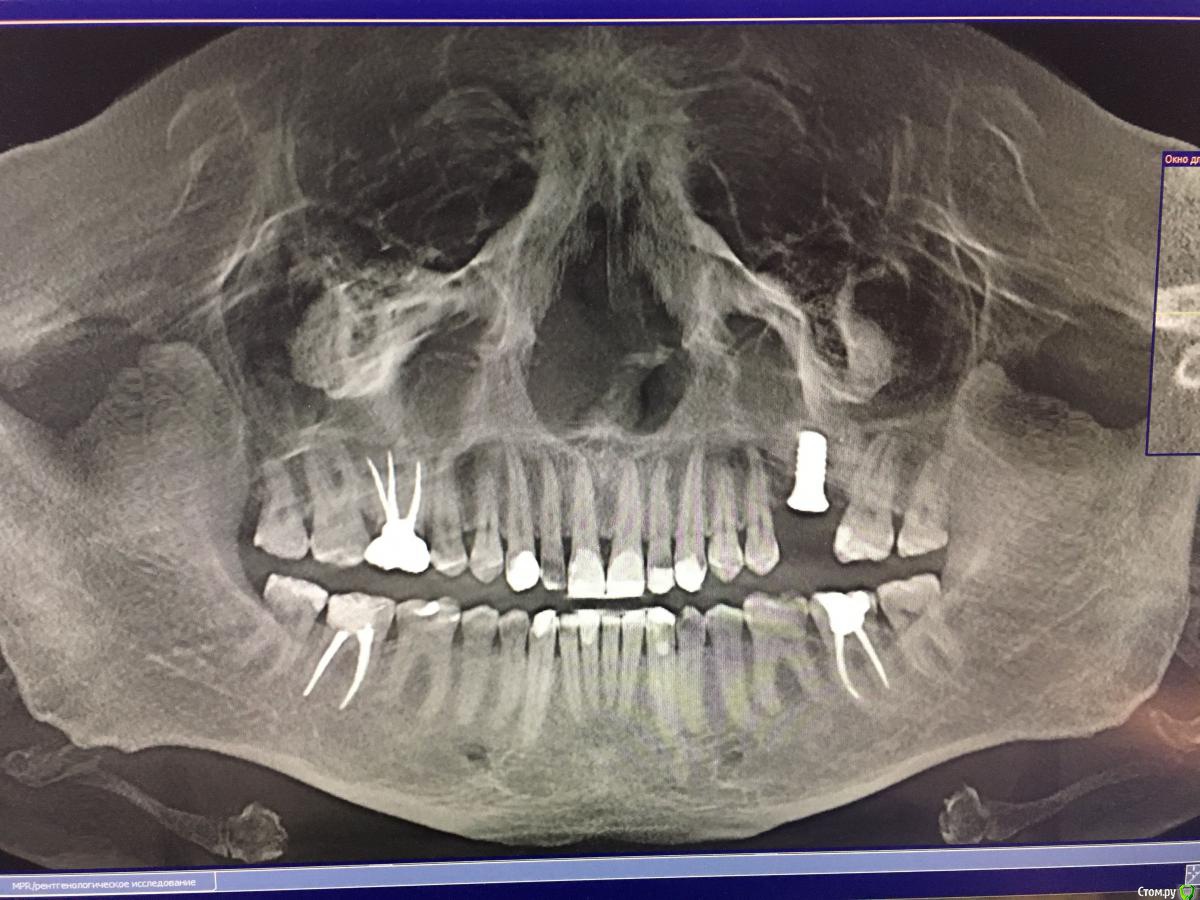

Геннадий1984 Опубликовано 5 мая, 2019 Автор Поделиться Опубликовано 5 мая, 2019 Прикрепляю фотографии Ссылка на комментарий

Геннадий1984 Опубликовано 5 мая, 2019 Поделиться Опубликовано 5 мая, 2019 Здравствуйте, прошу помочь советом. Зубами я начал заниматься в 27 лет, была сильная стираемость из-за не правильного прикуса. Сделал полную санацию, поставил металлические брекеты и три с половиной года их носил. Так как до установки брекетов зубы порядком стерлись, то после снятия нужно было поднимать прикус и восстановить эстетику на сколько это было возможно. Мой ортодонт не рекомендовала коронки, да и исходя из финансового положения решил поднимать прикус и восстанавливать зубы пломбировочным материалом. Часов за пять врач-скульптор "сваял" мне новые зубы и всё бы хорошо если бы пломбировочный материал держался больше года, но к сожалению опять всё обветшало. Особенно на нижней челюсти в переднем ряду слетают пломбы на фасаде. Замечу сразу, что чувствительности на холодное\горячее нет, даже у нижних пеньков, бруксизмом не страдаю. В сентябре прошлого года поставил имплант и в скором времени нужно будет ставить коронковую часть. Не могу понять как мне поступить, главная задача это эстетика, в остальном меня зубы устраивают. С 2012 года плотно общаюсь с ирригатором, электрической зубной щеткой и ополаскивателями как итог полностью прошла кровоточивость десен и забыл что такое кариес, но вот внешний вид(((. Вопросы: 1. Сначала поставить коронку на имплант, а затем поднимать прикус или наоборот?2. Существуют ли комбинированный вариант поднятия прикуса. То есть где-то коронки, а где-то поднять пломбировочным материалом?3. Если поднимают прикус, то это затрагивает все зубы без исключения? Следующим сообщением пришлю фотографии. Спасибо Ссылка на комментарий